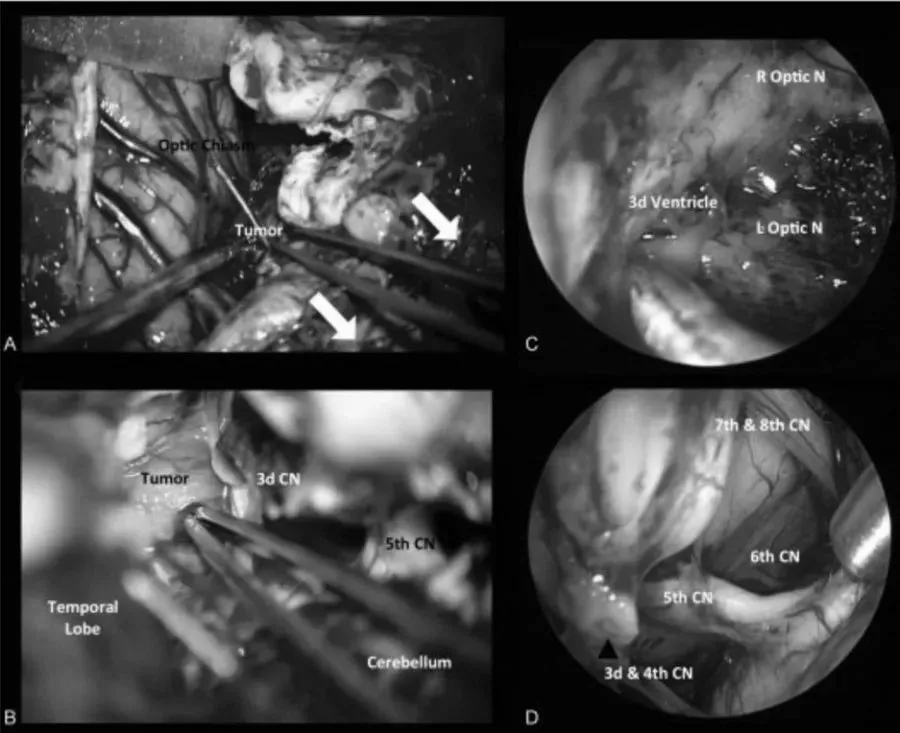

第一阶段,采用经神经内镜经鼻入路,对视交叉和神经进行减压,为后续处理奠定基础。然而随着肿瘤加速生长,新的视觉缺损相继出现,对下丘脑和第三脑室的压迫持续加重,需要再次手术切除。第二阶段,经后岩骨入路(即后迷路经天幕入路)可充分暴露肿瘤及周围解剖结构,包括第三脑室底部及侧壁、分支血管、视神经等。

手术过程中详细处理了后岩骨入路的相关技术要点及术中解剖细节,涵盖横窦-乙状窦连接部的后方移位、天幕切开时静脉结构的保护方式、肿瘤切除过程中第三脑室底部的辨认与保护,以及精细的多层次缝合关闭等步骤。

对于包括颅咽管瘤在内的复杂颅底肿瘤,福洛里希教授曾在来华专访中阐述其手术理念:"颅底手术的前提是进入颅底极深的区域。通常有两种选择:要么建立较大的手术通路,但这会增加患者风险,因为暴露的组织结构更多;要么尽量缩小手术通路,为了在内部仍保持良好视野,通常需要借助内镜来扩展手术视野。因此在我所做的绝大多数手术中,内窥镜是不可或缺的器械,我用它来观察开颅手术中未能直接暴露的结构。内窥镜与显微镜配合使用,几乎是颅底手术的完美组合,鉴于颅底手术的操作深度,内窥镜在颅底手术中是绝对必备的工具。"

然而无论是显微镜手术还是内镜手术,归根结底还是手术入路的选择问题。福洛里希教授表示:"选择合适的入路至关重要,神经内镜只是一种工具,可以用来进入深层区域、看到后方的盲区。它对某些适应症有优势,但并非适用于所有情况,某些病例可能需要神经内镜与显微镜联合手术治疗。"

颅底病变的复杂性决定了在某些情况下,单一手术方式无法实现大部分肿瘤的切除,有时需要两种方式协同配合来切除更多肿瘤组织。凭借高度的灵活性与操作敏捷性,福洛里希教授有时会在手术中同时运用三种器械。他不仅在经鼻入路手术中使用神经内镜,在开颅手术中同样辅助应用神经内镜。当肿瘤无法完整切除时,其放射肿瘤学团队将对残余肿瘤组织进行靶向消灭。对于颅底复发肿瘤,福洛里希教授同样主张依据不同病变位置,选择相应的手术入路进行切除。